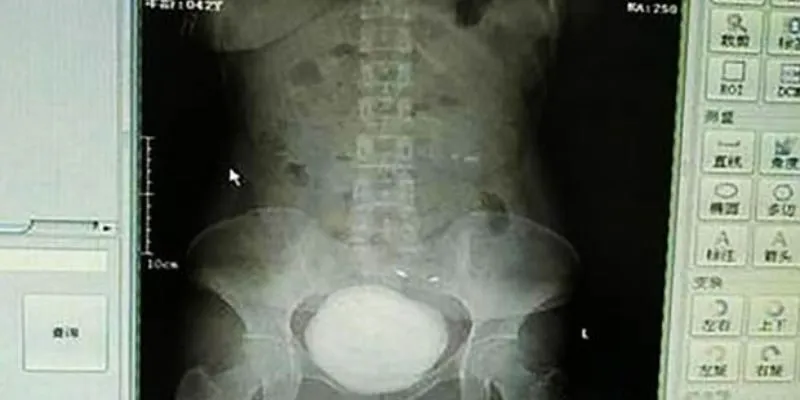

Khối Sỏi Khổng Lồ Trong Bàng Quang

Các bác sĩ tại bệnh viện Aksu First People, Trung Quốc, đã vô cùng kinh ngạc khi phát hiện ra rằng nguyên nhân gây ra tình trạng đi tiểu ra máu của cô Long không phải do một bệnh lý thông thường mà là một khối sỏi bàng quang khổng lồ. Khối sỏi này có đường kính lên đến 10cm và nặng khoảng 760g, tương đương với kích thước của viên bi sắt. Điều này khiến các bác sĩ không thể tin nổi rằng khối sỏi này lại tồn tại trong cơ thể cô Long suốt nhiều năm mà không được phát hiện.